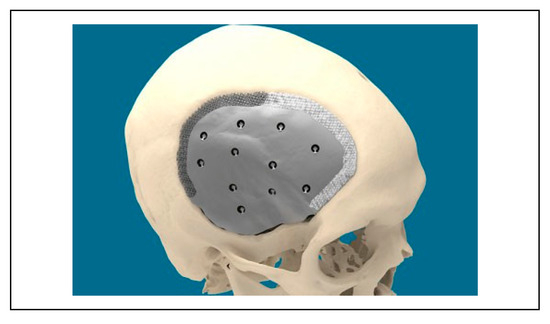

Ceramic 3D-Printed Titanium Cranioplasty

Technical Aspects